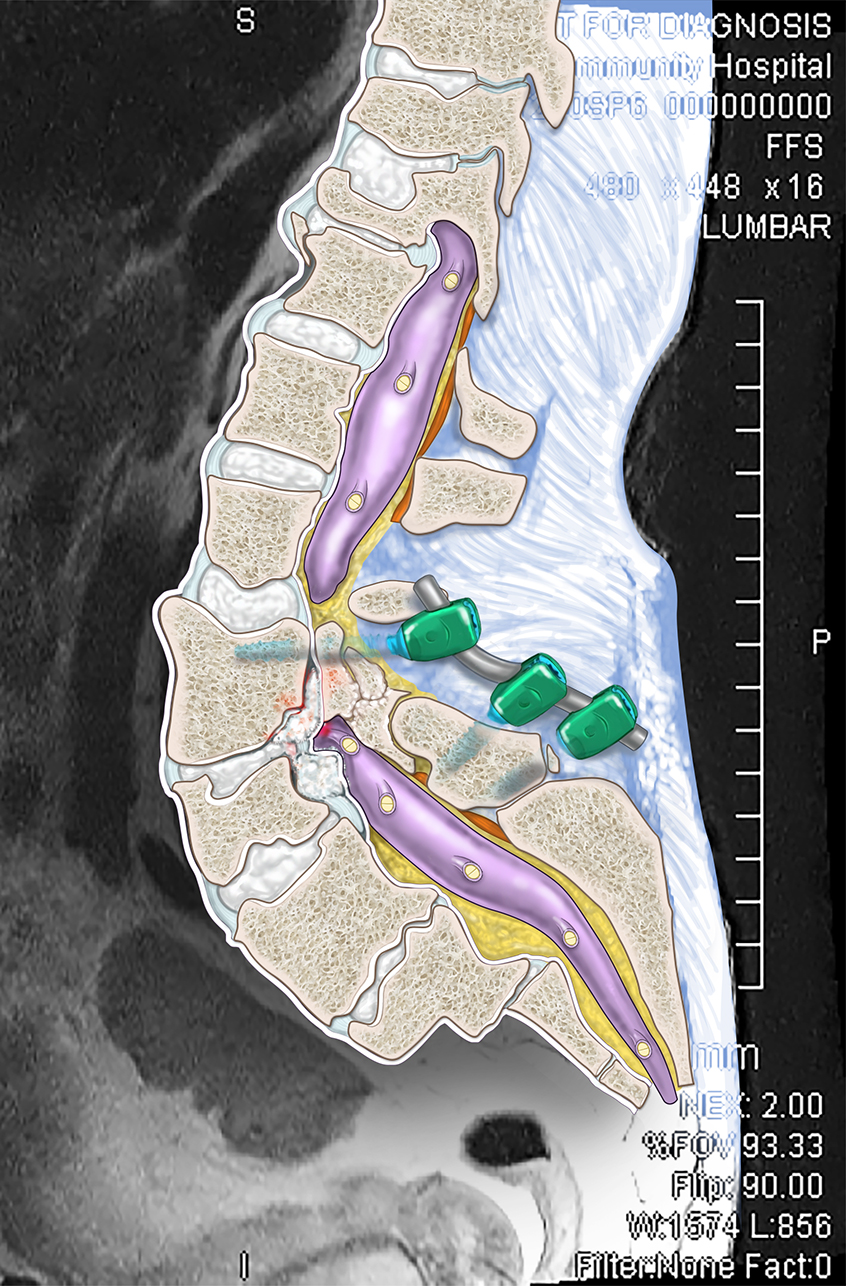

I am a medical illustrator! I wanted to be a doctor and was enrolled in premed, then received a few flyers for colleges in the mail for medical illustration. I decided to change my major from premed to medical illustration. I studied at two private colleges in a combined program for art and medicine.

I create medical illustrations, animations, interactive projects and timelines for physicians, attorneys, medical device and pharmaceutical companies to create illustrations for educational purposes.

I work a lot with attorneys to create medical demonstrative aids for insurance adjusters, mediations and trials. These medical demonstratives help to secure settlements for severely injured and families of decedents.

I am proud to educate people. To scientifically visualize what’s unseen by the naked eye for the general public!

Image Credits

Lindsay Coulter